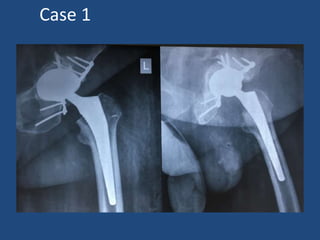

Case 1